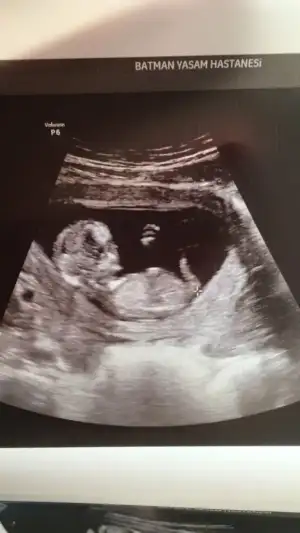

Bizim içinde yorum yapabilir misiniz 12+4 🥰 karından ultrason resimleri bunlar

Eklentiler

• 9233C909-3C3A-4298-8263-605B0E903418.webp

9233C909-3C3A-4298-8263-605B0E903418.webp

21,9 KB · Görüntüleme: 67

• FF8AAF11-D8EF-442F-9604-CA41F0B2AB4E.webp

FF8AAF11-D8EF-442F-9604-CA41F0B2AB4E.webp

21,6 KB · Görüntüleme: 65